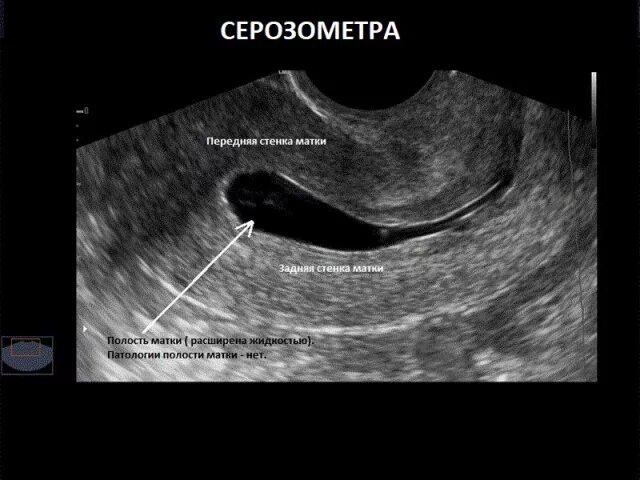

Как улучшить эндометрий